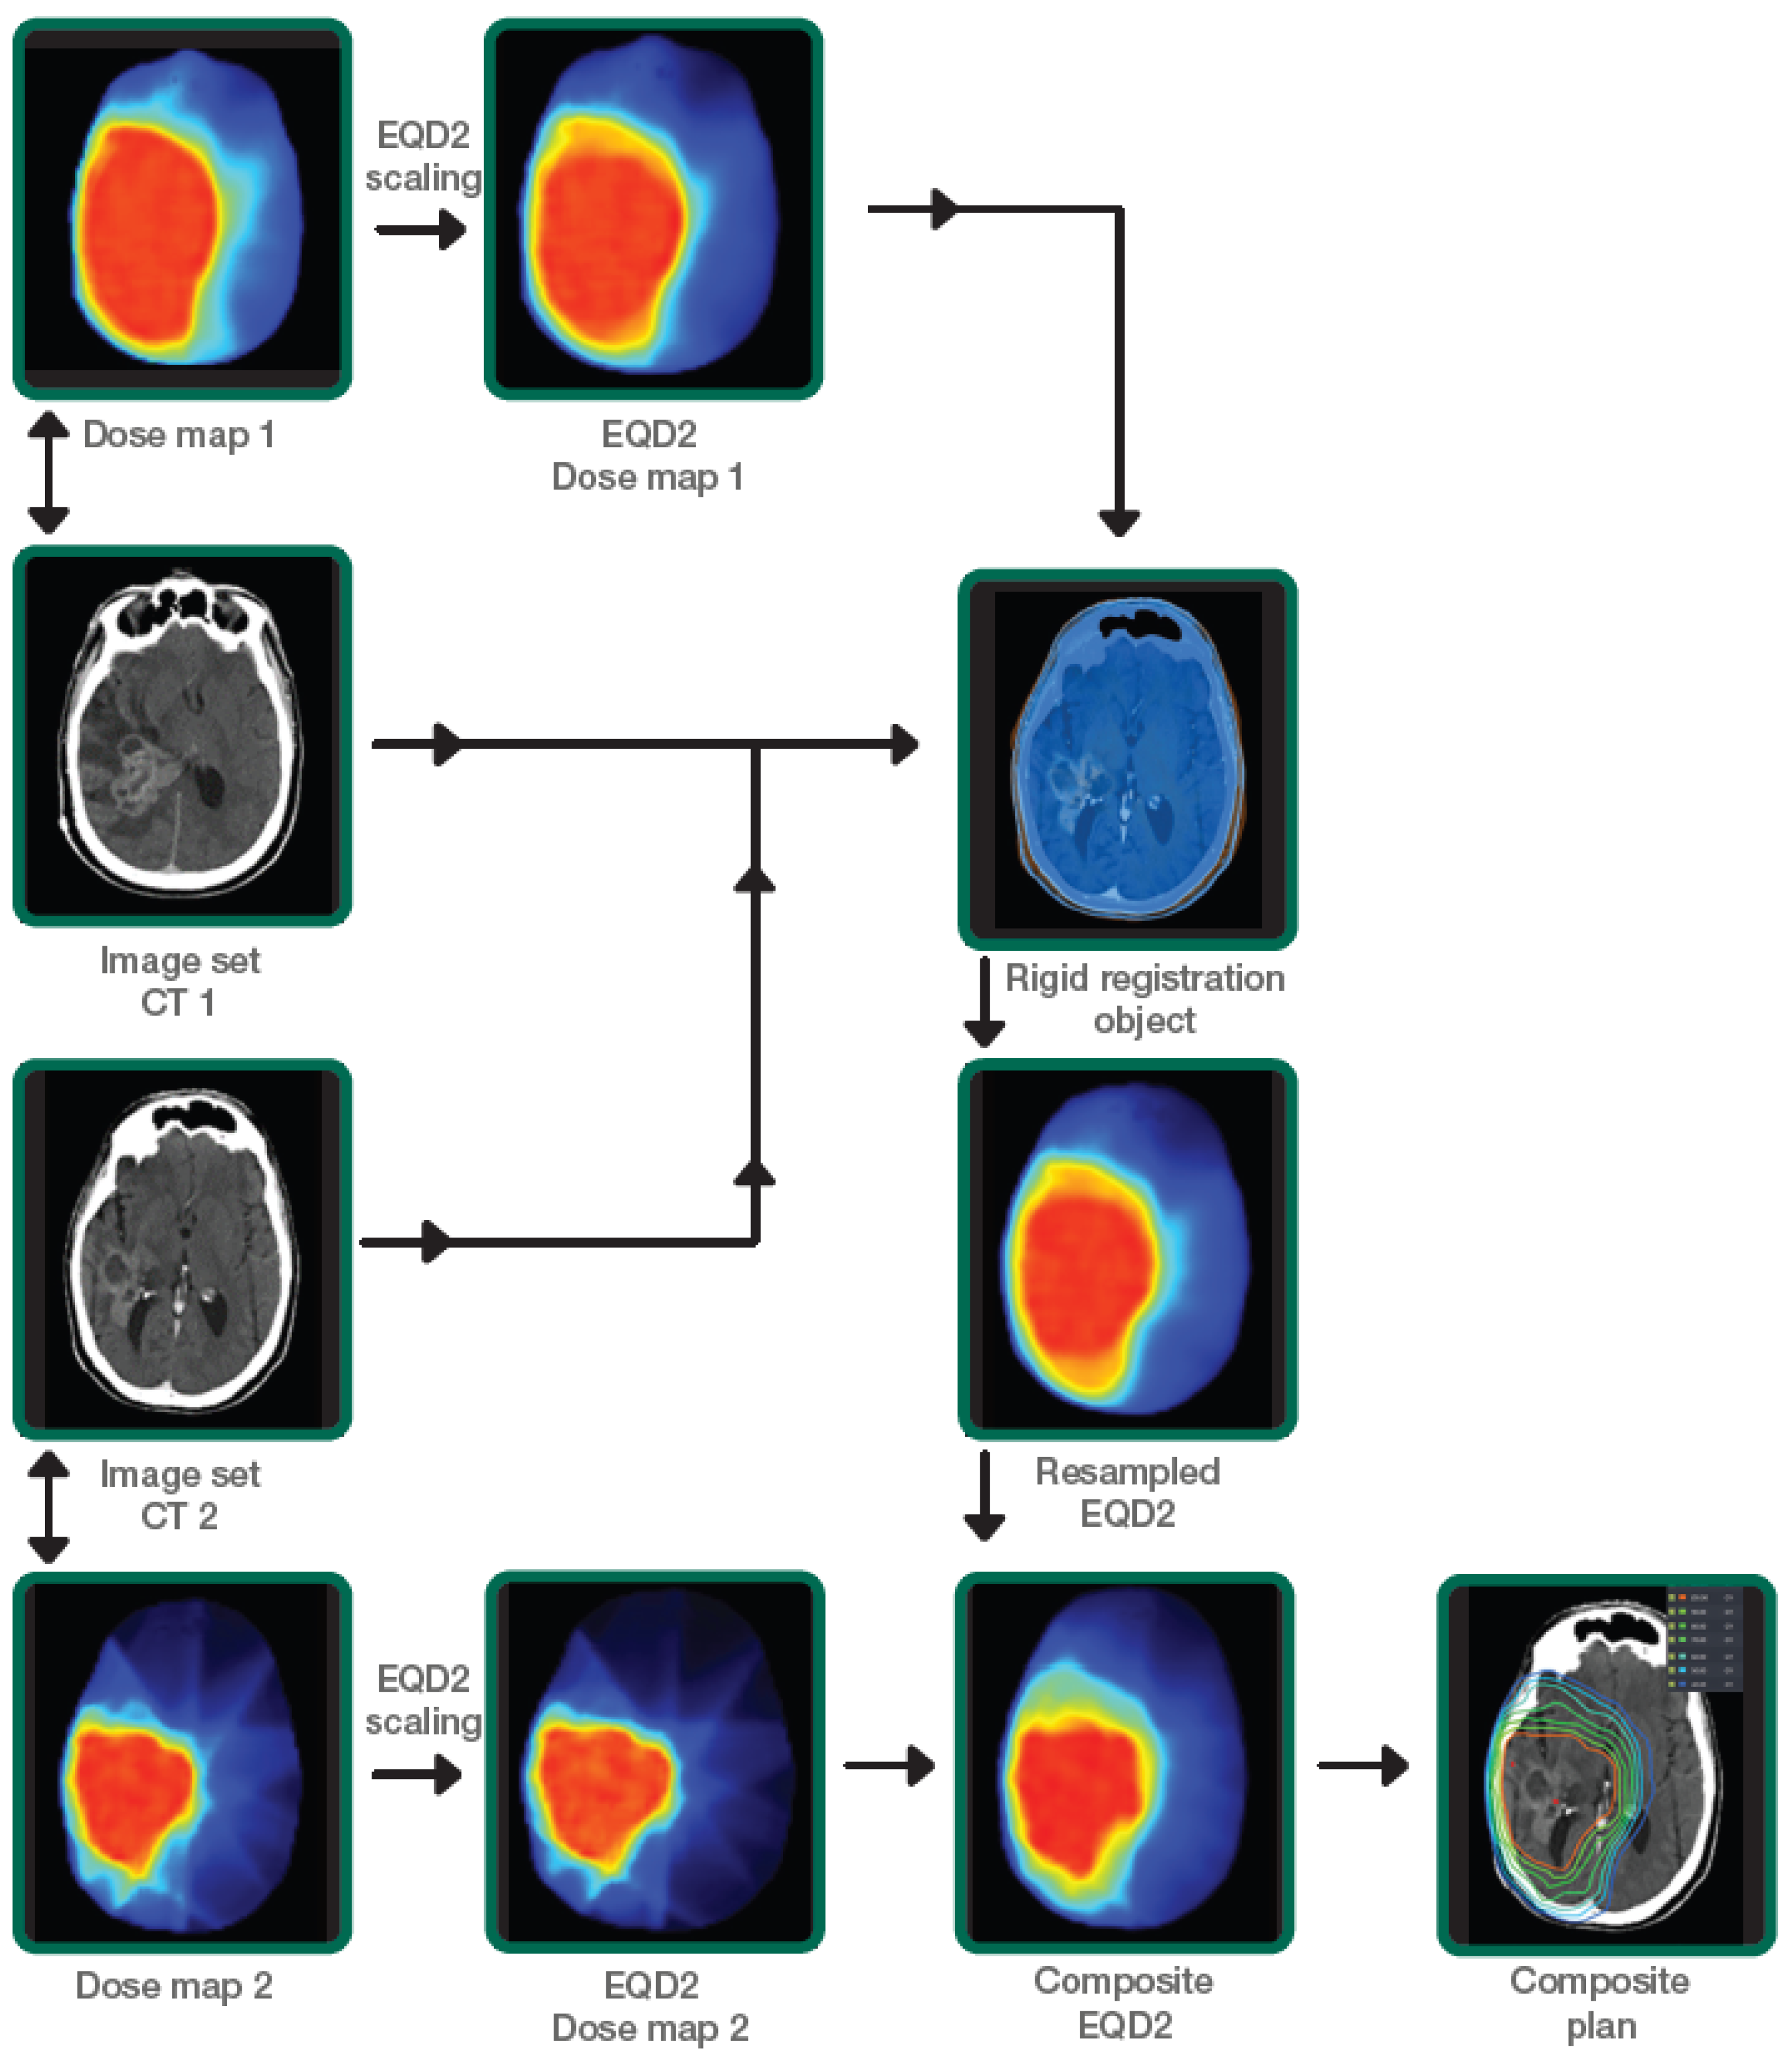

The two EQD2 dose distributions were combined using the dose summation workflow in Velocity AI™. The spatial relationship between the two 3D dose matrices was computed using rigid, with maximization of mutual information between the two CT image datasets. The rigid transformation was applied to re-sample the EQD2 dose distributions from the previous course to the most recent CT (reference CT) and summed to obtain the cumulative EQD2 dose distributions. Cumulative EQD2 distributions to each OARs from both plans were then evaluated. The following dose parameters were then extracted: mean, D0.03cc, D0.5cc, and D1cc EQD2 values for OARs (brain as defined as whole brain minus CTV, brainstem, optic chiasm, ipsilateral and contralateral optic nerves, ipsilateral and contralateral cochlea, and ipsilateral and contralateral hippocampus) and target volumes. Our departmental workflow is illustrated in Figure 1. Toxicity was defined as either acute (≤12 weeks after PRDR) or late (>12 weeks after PRDR) toxicity. Acute toxicities were monitored weekly during treatment. Follow-up 4–6 weeks after completion of radiotherapy and every 2–3 months thereafter included clinical evaluation and contrast-enhanced brain MRI. Toxicity was scored according to the National Cancer Institute CTCAE v5.0 criteria. Radiation necrosis was defined as new or growing enhancement in the area of prior radiotherapy, in which recurrent tumor was excluded. These cases were all discussed at the multidisciplinary tumor conference to gain a consensus from physicians amongst multiple specialties, including neuroradiology, neurosurgery, neuro-oncology, and radiation oncology, with all treatment plan information and overlay between dose and imaging to differentiate tumor progression from radiation necrosis. Factors contributing to a diagnosis of radiation necrosis included spontaneous resolution without intracranial anti-tumor therapy, lack of elevated relative cerebral blood volume on dynamic susceptibility contrast MRI perfusion, and/or lack of mass-effect.

Figure 1.

Institutional workflow demonstrating the calculation of EQD2 dose summation using prior dose and PRDR dose distributions.